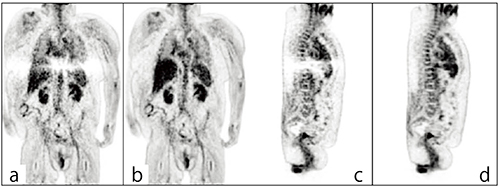

図2 従来法(a,c)とxClean(b,d)による画像比較

従来法では散乱線に伴うアーチファクトの影響で肝上縁に広範囲なデータ欠損が出現しているが,xCleanではアーチファクトの抑制効果を認める。